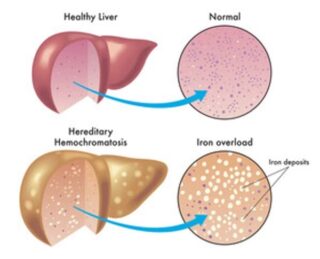

Hereditary liver disorders

"Hereditary liver disorders are genetic conditions that impact the normal functioning of the liver, often stemming from inherited genetic mutations. These disorders can manifest in various ways, leading to liver damage and complications.